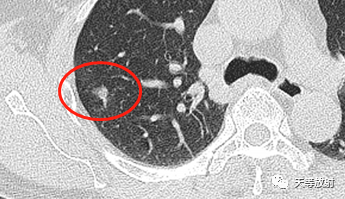

18d907124326f11affdbc1d6e92eed95.png

实性结节呈分叶状改变,邻近胸膜增厚,有牵拉改变,凹陷征。